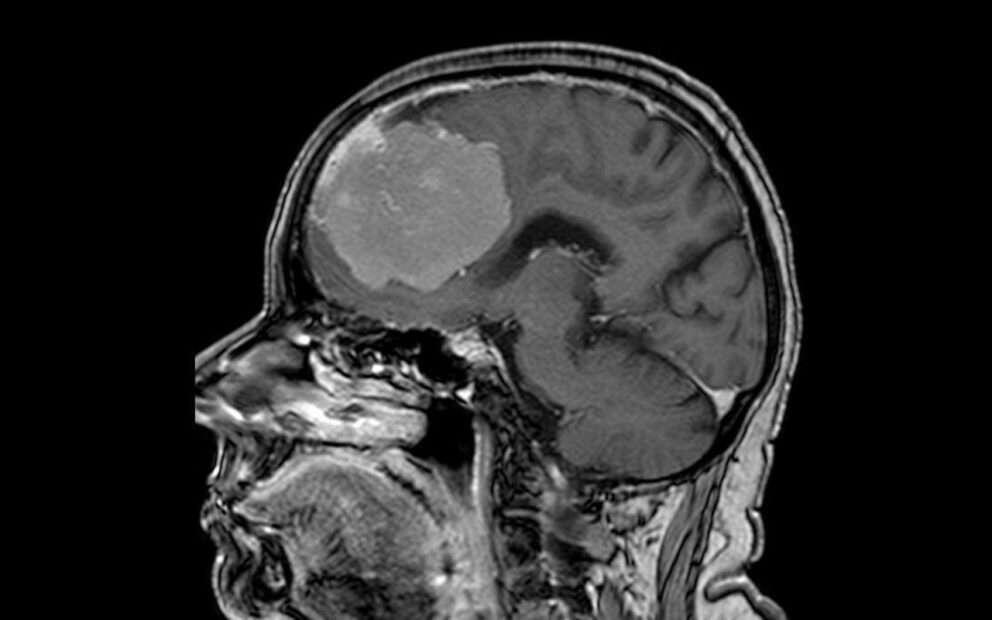

Врачи удалили у пенсионерки опухоль размером с грейпфрут. Ее обнаружили в лобных долях мозга. Об этом в среду, 21 мая, сообщили в пресс-службе министерства здравоохранения Воронежской области.

По информации структуры, 80-летняя женщина поступила в больницу скорой медицинской помощи (БСМП) №1 с подозрением на инсульт – у нее наблюдались проблемы с речью и слабость в правой руке. Однако при стандартном обследовании с помощью компьютерной томографии стало понятно, что инсульта нет. Специалисты обнаружили опухоль в обеих лобных долях мозга размером 6x7x8 см.

Дополнительное исследование с контрастом показало, что опухоль окутываала переднюю мозговую артерию, прорастала в переднюю треть одного из наиболее крупных венозных коллекторов головного мозга и закрывала его.